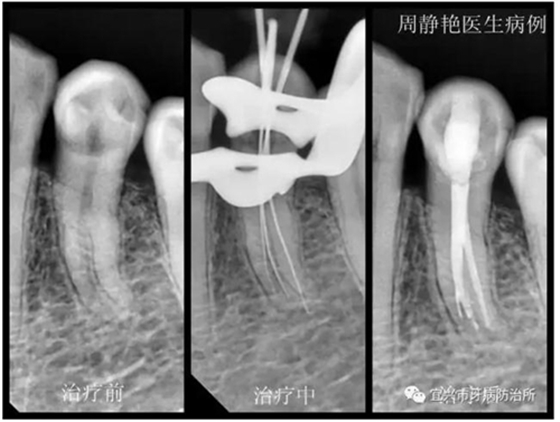

患者鄭女士,61歲,一個(gè)月以來(lái),左下后牙經(jīng)常冷熱刺激痛,一周來(lái)疼痛加劇,夜間痛明顯,冷刺激更甚。經(jīng)X光檢查,34根尖無(wú)明顯陰影,根管形態(tài)復(fù)雜,疑是根中分為雙根管或C形根管。上障,34局麻下去腐,開髓,拔髓,根管探查,疑是3根管,拍診斷絲片。再次根管蕩洗,熱牙膠充填,流動(dòng)樹脂墊底,樹脂充填。囑一月后復(fù)查,冠修復(fù)。